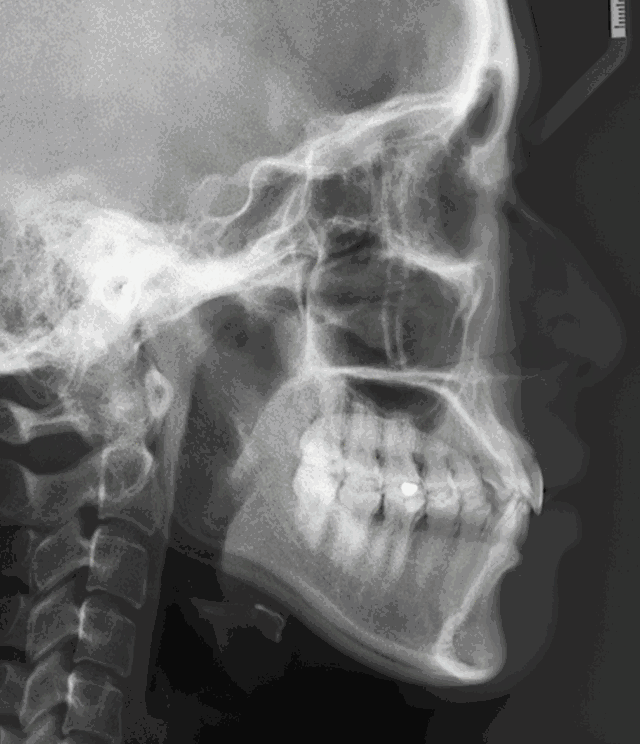

【來(lái)來(lái)來(lái)??!教你看出側(cè)臉的突嘴形態(tài)】:?↓↓

骨性突嘴側(cè)臉形態(tài)動(dòng)圖